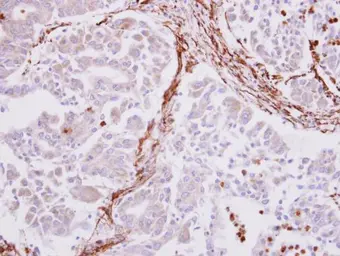

alpha smooth muscle Actin antibody detects alpha smooth muscle Actin protein at cytoplasm on human liver carcinoma stroma by immunohistochemical analysis.

Sample: Paraffin-embedded liver carcinoma stroma.

alpha smooth muscle Actin antibody (GTX100034) diluted at 1:500.

Antigen Retrieval: Trilogy™ (EDTA based, pH 8.0) buffer, 15min